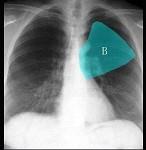

如图所示正常胸部X线影像图像上,该英文字母所代表的肺段为 ( )A.尖段B.后段C.尖后段D.舌叶上段E.前段

问题 如图所示正常胸部X线影像图像上,该英文字母所代表的肺段为 ( )

选项 A.尖段 B.后段 C.尖后段 D.舌叶上段 E.前段

答案 E